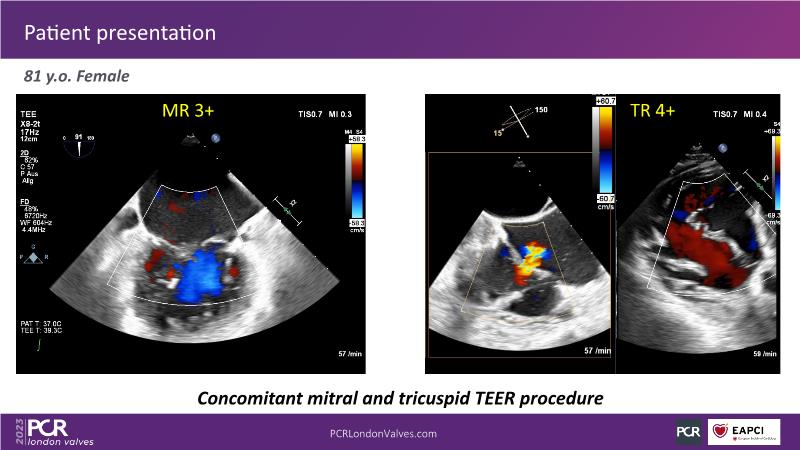

This session explores the features of the PASCAL Precision and the EVOQUE tricuspid replacement systems through simulators and case presentations, while a panel of experts discuss the technology, witnessing live demonstrations of treating mitral and tricuspid regurgitation patients.

- To learn about the differentiating features of the PASCAL Precision system showcased in a series of simulators alongside case presentations

- To interact with a panel of experts discussing the PASCAL Precision system technology and showcasing, live, its different key features in action and how they help treat mitral regurgitation and tricuspid regurgitation patients